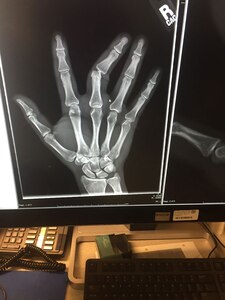

By Airman 1st Class Christopher R. MoralesJBER Public Affairs"My finger went ba-doink," the noncommissioned officer said as he demonstrated an unnatural bend for any digit.Air Force Master Sgt. Robert Wagner, 773d Civil Engineer Squadron primary security manager, and a musician and athlete, lost